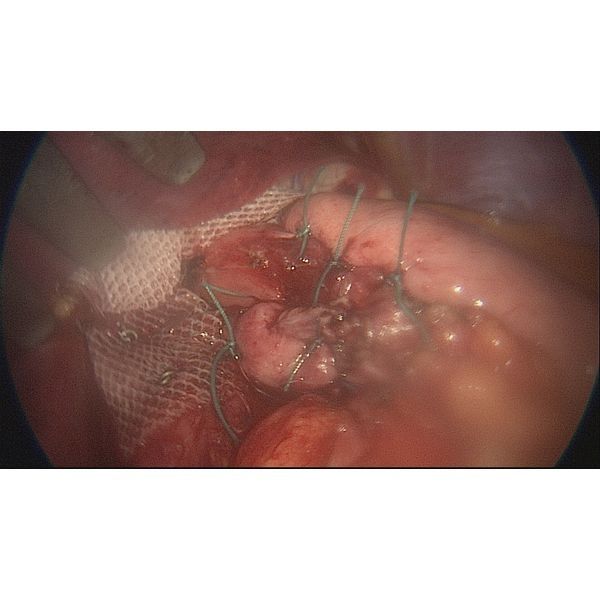

Пациентка прошла интенсивный курс предоперационной подготовки, после чего ей провели лапароскопию, в ходе которой:

- удалили грыжу;

- восстановили правильную позицию пищевода и желудка;

- создали антирефлюксную манжету по Тупе (для укрепления нижнего пищеводного сфинктера обернули верхнюю часть желудка вокруг пищевода на 270°);

- восстановили пищеводное отверстие диафрагмы и укрепили его с помощью сетчатого эндопротеза.